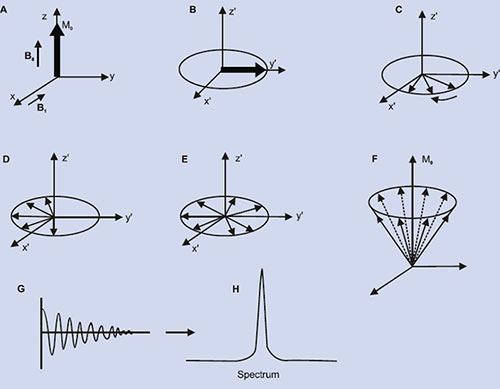

Fig. 1.1: (A) Spin orientation in human tissue sample in the absence of external magnetic field (Bo). (B) In the presence of an external magnetic field the spins orient themselves along the magnetic field direction (z-axis) with some spins in the parallel and some anti-parallel state with respect to the magnetic field. Transition between the energy levels is possible by the application of RF energy (equivalent to ∆E) applied at the resonant frequency (ν0) of the proton nucleus.

The magnetization arising from different number of nuclei (say proton) present in tissues is the so-called net (or bulk) magnetization M0 (=Mz) which is parallel to the external magnetic field, B0. A strong radio-frequency field B1 applied along x-axis, tips M0 away form z-axis (Fig. 1.2A). The duration and power of the RF pulse determines the direction of M0 after the pulse. If a so-called 90°x or π /2 pulse is applied, M0 points along the positive y-axis (Fig. 1.2B), i.e. the z-magnetization (longitudinal) is now transferred into a transverse plane. The Larmor frequencies of the various (proton) nuclear magnetic moments vary and as a consequence, the vector M (actually Mxy) now splits into its components (Fig. 1.2C) in the xy plane and produce a voltage signal. A plot of the time dependence of the intensity of the y-component of the Mxy magnetization (that is, the voltage induced in the receiver coil) as a function of time is known as free induction decay, FID (Fig. 1.2G). Thus, FID represents the time evolution of the transverse magnetization. It is necessary to analyze this time-domain signal f(t), into its individual frequency components, F(ω). This is accomplished by a mathematical formulation, known as the Fourier transformation (FT), which is given by

This allows not only the extraction of the individual frequencies but as well as their associated amplitudes, which are proportional to the spin density at a particular spatial location (Fig. 1.2H).

Fig. 1.2: Spin magnetization rotated away from the main magnetic field (Bo). (A) By the application of an RF field B1 along the x– direction, the magnetization (Mxy) is rotated to y–direction (B). Thereafter, the nuclei (spins) continue to rotate in the transverse plane at different rates, (C), (D), (E), causing their resultant magnetization Mxy to diminish (T2 process). Meanwhile spin-lattice relaxation (T1) process causes the nuclei to realign along Bo(F). (G) the free induction decay (FID) resulting from T2 process and its Fourier transform (H).